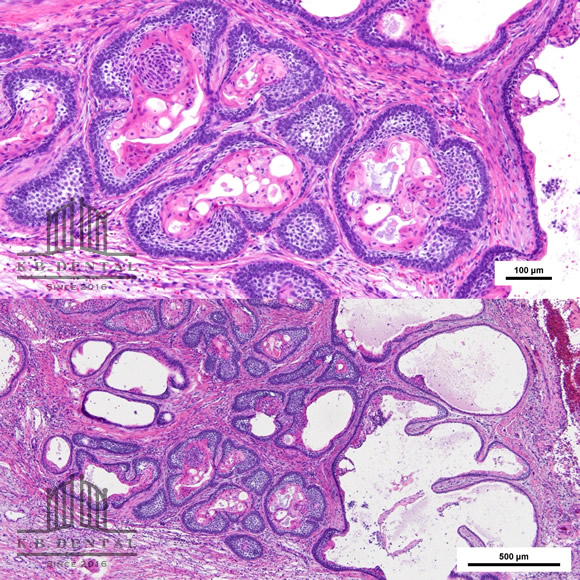

エナメル上皮腫(濾胞型)

術後2年経過の最も典型的なエナメル上皮種です。再発率が非常に高いので最低でも5年以上の経過観察が必要となります。今回は摘出術と一部健常域まで辺縁切除(骨を削る)を行いました。

3枚目 左:摘出物の腫瘍本体と割断像 右:割断して内容物が充実性である事がわかります。

4枚目 上:高倍率 下:低倍率 腫瘍実質の胞巣が濾胞状を示しているのがわかります。